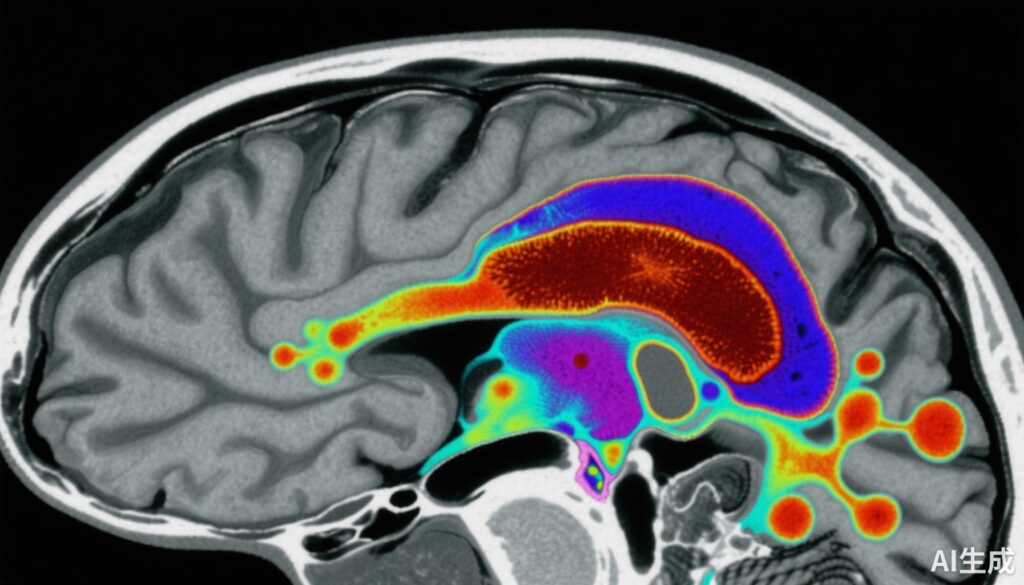

Nghiên cứu này so sánh 159 đối tượng: 80 đối chứng khỏe mạnh và 79 cá nhân mắc schizophrenia giai đoạn sớm (bao gồm cả bệnh nhân chưa sử dụng hoặc không sử dụng thuốc chống loạn thần). Độ dễ bị hấp thụ từ SN-VTA được đo định lượng bằng MRI định lượng độ dễ bị hấp thụ (QSM), cung cấp một dấu hiệu không xâm lấn của mức sắt mô.

Cuối cùng, ở 40 bệnh nhân schizophrenia, khả năng tổng hợp dopamine trong khu vực bẹn được đo bằng PET [18F]-DOPA, cho phép phân tích tương quan giữa mức sắt SN-VTA và hoạt động dopaminergic.

1. Mức độ dễ bị hấp thụ SN-VTA giảm ở bệnh nhân schizophrenia: Bệnh nhân có giá trị QSM thấp hơn đáng kể ở SN-VTA (kích thước hiệu ứng d = -0.66, khoảng tin cậy 95% -0.98 đến -0.34) so với đối chứng. Điều này chỉ ra mức sắt não giảm ở vùng dopaminergic quan trọng này.

3. Tương quan nghịch giữa sắt SN-VTA và khả năng tổng hợp dopamine trong khu vực bẹn: Ở bệnh nhân schizophrenia, mức độ dễ bị hấp thụ SN-VTA thấp hơn có liên quan đáng kể với khả năng tổng hợp dopamine cao hơn trong khu vực bẹn (Ki cer) (hệ số tương quan r = -0.44). Mối quan hệ này vẫn có ý nghĩa sau khi kiểm soát cho melanin não và myelin.

4. Tính đặc hiệu theo vùng: Các tác động rõ ràng nhất được xác định ở phần ventral của SN-VTA, một vùng liên quan đến việc điều chỉnh tông màu dopaminergic trong khu vực bẹn.